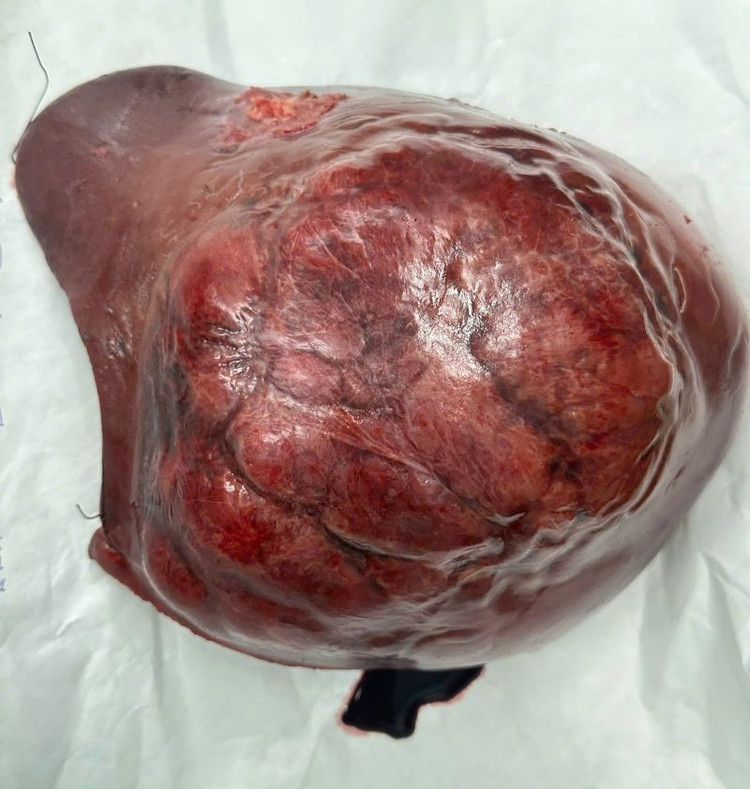

Ở giai đoạn hai, ê kíp phẫu thuật đã thực hiện cắt bỏ toàn bộ gan phải mang khối u, với khối lượng hơn 1,5 kg. Ca mổ thành công, bệnh nhân hồi phục tốt và không gặp biến chứng suy gan do thiếu hụt thể tích gan chức năng.

cat-gan-2-dg-3.jpg

gan-2.jpg

Gan với khối u gan phải khổng lồ và sau khi cắt bỏ gan phải - Ảnh BVCC